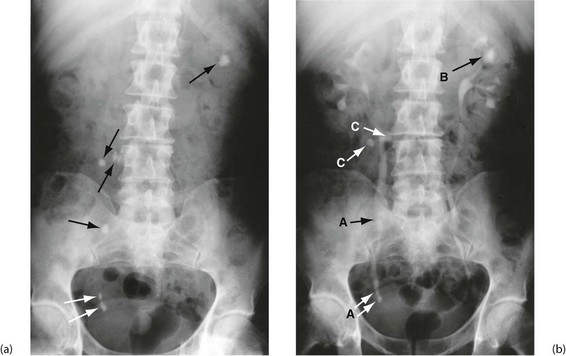

Plain abdominal radiology: Most abdominal films are taken with the patient supine. Bowel is visible when it contains gas (Figs 5.3 and 5.4); normal small bowel is less than 3 cm wide and tends to occupy the centre of the abdomen. When dilated, it shows transverse folds (plicae circulares) which completely cross the lumen. The colon usually lies peripherally and has haustrations; these folds only partly traverse the lumen (Fig. 5.3). Normal colon is less than 6 cm wide and often contains faecal lumps with a mottled appearance. Further reading about this topic is available from: http://www.studentbmj.com/topics/clinical/imaging_techniques.php.

Free intraperitoneal gas: Free gas is diagnostic of bowel perforation except after recent laparotomy. A horizontal beam chest or upper abdominal X-ray with the patient erect is the most useful method of demonstrating it as a radiolucent layer beneath the diaphragm (see Fig. 19.8, p. 275). The layer can be very small but is often obvious. Perforation can also be confidently diagnosed when the inside and outside of the bowel wall are both outlined by radiolucent shadows, but this is rare (Rigler's sign, Fig. 32.7, p. 413). Where the result is doubtful or the patient too ill to sit or stand, he or she should be placed in the right-side raised lateral decubitus position (i.e. lying on the left side) for 10 minutes. A horizontal beam X-ray taken across the table can then reveal as little as 2 ml of gas above the lateral liver border (Fig. 5.4).

Fig. 5.8 Plain abdominal X-ray and IVU compared

(a) A plain abdominal film and (b) an intravenous urogram (IVU) of the same patient showing urinary tract stones. In the plain film, several calcified opacities (arrowed) are seen. From the IVU, in which the pelvicalyceal systems and ureters contain contrast material, it can be seen that three stones A lie within the lower right ureter and stone B lies within the upper calyces of the left kidney. On the right side, two other opacities C are seen to lie outside the urinary tract, probably representing calcified lymph nodes in the small bowel mesentery